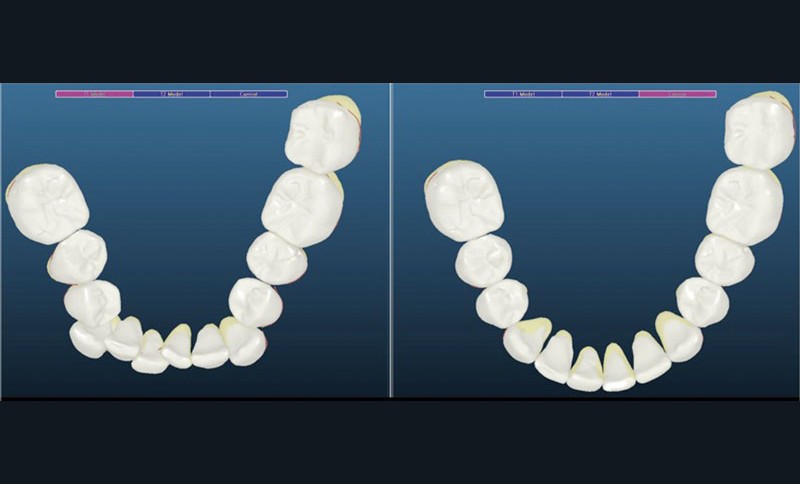

Un appareillage Damon métal a été mis en place, réalisé à partir d’un set up numérique Insignia pour obtenir un contrôle précis des torques et de la forme d’arcade et réduire le temps de finition grâce à un collage indirect très précis.

L’objectif, en utilisant la technique Insignia est de réduire le temps de traitement de 28 à 18 mois avec 12 rendez-vous (fig. 5 à 14).